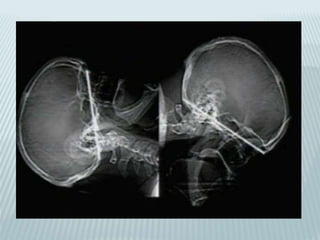

STYLOID SEGMENT

 Styloid process develops after birth(like

mastoid)

 Stylomastoid canal